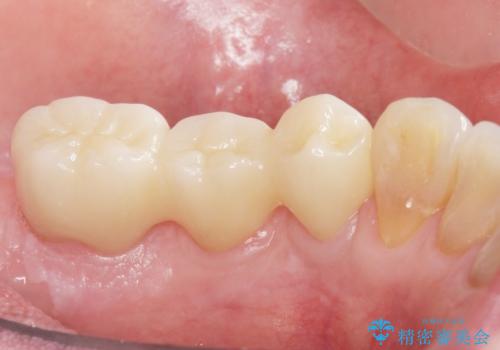

[MTMを行い歯の神経を保存] 歯周補綴ブリッジ

![[MTMを行い歯の神経を保存] 歯周補綴ブリッジの症例 治療後](https://seimitsushinbi.jp/wp/wp-content/uploads/2021/04/75330aaa19199048b71f28658fe46b5b-1-500x350.jpg?v=1618452202)